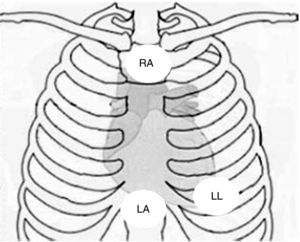

Physical examination showed no abnormalities. Diagnostic exams included 12-lead electrocardiogram (ECG), which showed a pattern of right bundle branch block, together with epsilon waves and T-wave inversion in leads V1–V3 (Figure 1). In order to characterize the typical ARVC alterations, a right-sided precordial lead ECG and a modified Fontaine ECG were performed, the latter with the following placement of electrodes: the right arm electrode over the manubrium, the left arm electrode over the xiphoid and the left leg electrode in the area corresponding to V4, at a recording speed of 25 mm/s and voltage of 10 mm/mV (Figure 2). Both methods clearly showed epsilon waves, especially the modified Fontaine ECG (Figure 3A and B). Two- and three-dimensional transthoracic echocardiography at our institution showed severe right ventricular dilatation and hypokinesia, with prominent apical trabeculae and false tendons and saccular dilatations in the ventricular free wall (Figure 4A and B). Cardiac magnetic resonance imaging revealed small foci of subepicardial fatty infiltration in the right ventricular free and inferior walls, interventricular septum and left ventricular free wall; late enhancement study showed focal enhancement in the interventricular septum consistent with fibrosis (Figure 4C and D).

Placement of electrodes in Fontaine ECG. LA: left arm electrode; LL: left leg electrode; RA: right arm electrode.